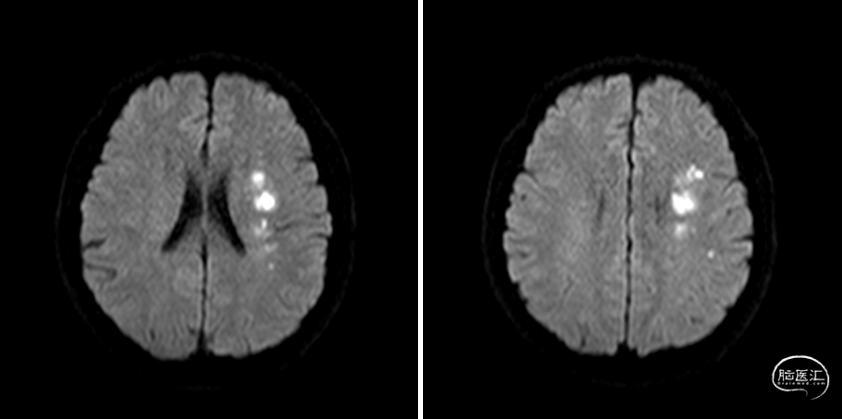

DWI

重要影像结论:左基底节区、放射冠区脑梗死,左大脑中动脉M1末端狭窄。

DSA

重要影像结论:左大脑中动脉M1末端重度狭窄。